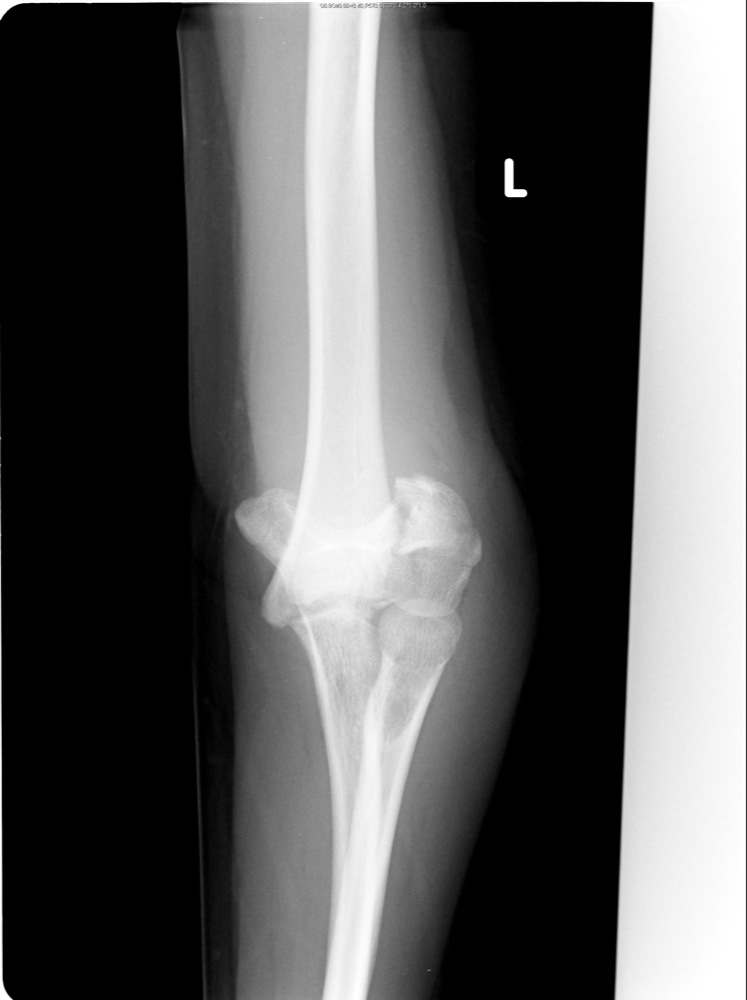

Left Elbow X Ray

File:X-ray of normal elbow by lateral projection.jpg - Wikipedia Elbow series | Radiology Reference Article | Radiopaedia.org X-ray Left Elbow Joint AP & Lateral View | Test Price in Delhi | Ganesh Diagnostic 12,736 Elbow X Ray Images, Stock Photos & Vectors | Shutterstock | Left Elbow X Ray